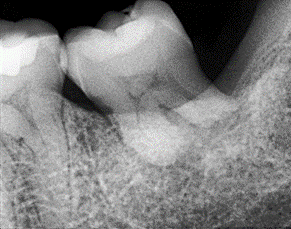

En las citas de seguimiento, se realizó la remoción de la férula. Se observó una

adecuada recuperación del tejido blando en términos de coloración y textura, sin alteraciones funcionales. Las pruebas térmicas arrojaron resultados negativos, sin respuesta del órgano dentario. Una radiografía digital de control (Figura 2) evidenció signos de reabsorción radicular, con un éxito clínico estimado en un 70%. Este hallazgo resalta la viabilidad de esta técnica incluso en dientes maduros, evitando la necesidad de extracción de múltiples órganos dentarios.

Fig 2 Radiografía periapical digital de control